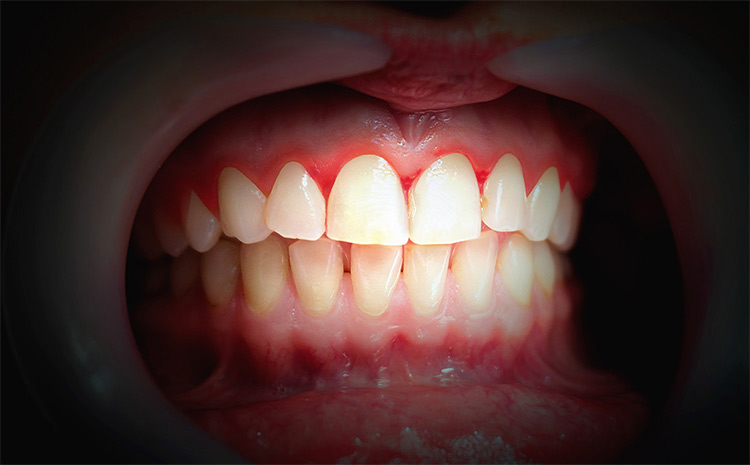

Viêm nướu

Đây là một bệnh về đường răng miệng rất dễ gặp phải, gây ra hôi miệng và chảy máu chân răng. Nguyên nhân gây ra viêm nướu thường là do vệ sinh không đúng cách, vi khuẩn có cơ hội tích tụ trong nướu khiến nướu răng xuất hiện những mảng bám, chảy máu và sưng tấy đỏ. Những mảng bám này sẽ dần bị vi khuẩn phân hủy sẽ khiến hơi thở có mùi hôi khó chịu.

Ngoài ra, khi bị viêm lợi, bạn cũng có cảm giác đau khi nhai thức ăn, lung lay nhẹ chiếc răng gần đó do viêm dây chằng quanh răng,…

Bệnh có tiến triển nhanh, phức tạp, phát hiện sớm và có cách điều trị bệnh phù hợp. Nếu không, bệnh có thể để lại biến chứng như viêm nha chu. Chứng hôi miệng cũng sẽ tiếp diễn nặng nề hơn, khó có thể cải thiện tận gốc.